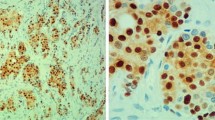

TMA slides were deparaffinized in xylene and rehydrated through a ladder of graded ethanol (absolute ethanol, 95%, 80% and distilled water). For detection of cyclin D1 (RM-9104-S; NeoMarkers), antigen retrieval was performed in a microwave oven for 10 min (750 W) + 15 min (350 W) with the use of a TE (Tris–EDTA pH9 buffer). After antigen retrieval, all TMA slides were processed in an automatic immunohistochemistry staining machine according to standard procedures (Autostainer, Dako, Sweden).

All cyclin D1 stainings were scored by one investigator (Ahlin C) blinded to all clinical information during scoring. Cells were manually counted in high-power fields. Only unequivocal nuclear staining was accepted. Hot spots were chosen for evaluation, and a minimum of 200 cells per patient were counted. Staining procedure and scoring of ER, PR, Ki-67, cyclin A, cyclin B, cyclin E, and HER2 have been described previously [51–53].